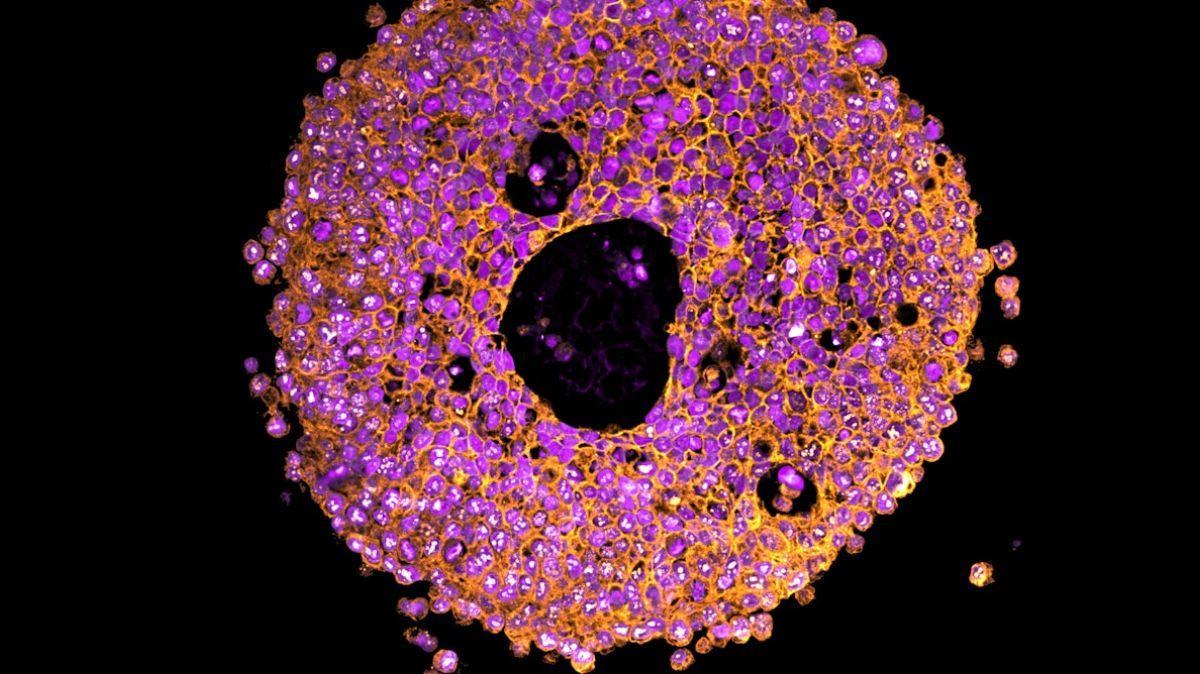

Imagen de un organoide placentario bajo el microscopio. / Crédito: Claire Richards.

En un nuevo estudio publicado en la revista Nature Communications, los investigadores describen un modelo de organoides placentarios bioprotintados, que reproducen con mayor fidelidad la microestructura y la diferenciación celular de la placenta en sus etapas iniciales.

El equipo de especialistas, liderado por Lana McClements y Claire Richards, utilizó una "biotinta" seleccionada específicamente y compuesta por células placentarias vivas, conocidas como trofoblastos. Mediante una bioimpresora 3D, depositaron esta mezcla capa por capa para construir una estructura tridimensional: este organoide no solo sobrevive, sino que también se comporta de manera muy similar al tejido placentario humano.

Sin embargo, a diferencia de los organoides tradicionales cultivados en geles derivados de animales, el método bioprotintado permite controlar con mayor precisión la composición y la arquitectura de la matriz, influyendo en cómo las células se diferencian y permitiendo una complejidad nunca antes alcanzada para su estudio.